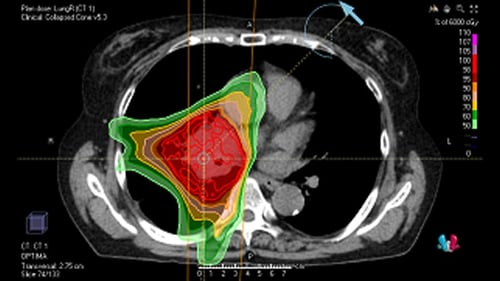

・肺がん

手術不能の場合や縦隔リンパ節に転移がある場合などに根治的放射線治療の適応となります。基本的に化学療法と同時併用で行いますが、年齢や全身状態などを考慮して放射線治療単独となる場合もあります。当院ではIMRTを積極的に行っており、副作用の低減と治療効果の向上を図っています。治療は抗がん剤と併用の場合、標準的に30回、放射線治療単独の場合は33~35回程度行います。副作用は皮膚炎、放射線食道炎(嚥下時違和感、痛み)、放射線肺炎(咳、発熱、呼吸苦など)が主体です。(図:肺がんに対するIMRT)

早期肺がんについては、多方向から集中的に放射線を当てる定位放射線治療を行っております。週2回、2週間程度の治療となります(部位により期間が長くなる場合があります)。手術に匹敵する効果が期待される治療です。副作用は治療期間中にはほとんどありませんが、治療後時間がたってから放射線肺炎や肋骨骨折が起こることがあります。(図:肺がんに対する定位放射線治療)

いずれの治療においても、呼吸により病変の移動が大きい場合には、呼吸同期照射を併用し、副作用の低減をはかっています。